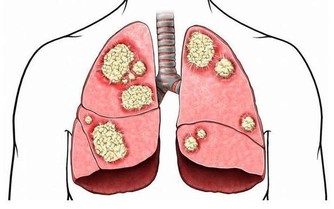

根據英國營養學家的研究發現,每星期食用西蘭花,有助於預防前列腺癌,究其原因,則是西蘭花內含有一種“抗癌因子”,能夠有效保護男性的前列腺免受癌症的襲擊。此外,除西蘭花外,同屬十字花科的菜花、紫甘藍,抗癌效果也不差,男性也該多吃。

對於男性的前列腺來說,最怕遇到的就是前列腺充血的情況,因為這往往會誘發前列腺炎或是前列腺癌。